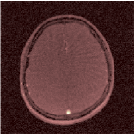

VI-E In-vivo experiments

Two sets of experiments were conducted here: first, we used the 2D and 3D acquisition sequences for scanning a healthy volunteer’s brain (real-world acquisitions). Figures 6 and 7 display the parametric maps reconstructed from 2D spiral and radial readouts. We computed the T1, T2 and proton density (PD) maps using baseline reconstruction algorithms ZF, VS, LR, FLOR, AIR-MRF and our proposed LRTV. While baselines use DM either for quantitative inference or also during reconstruction (i.e. AIR-MRF), we further compare the DM-free LRTV’s performance when cascaded to DM, KM and MRFResnet for quantitative inference. For the 3D spiral acquisitions we compared LRTV and its closest competitor VS in Figure 8. Outcomes from other tested algorithm are displayed in the supplementary materials (Figure S5). Since FLOR does not use dimensionality-reduction, our system ran out of memory during 3D reconstruction; hence results are not reported in this case.